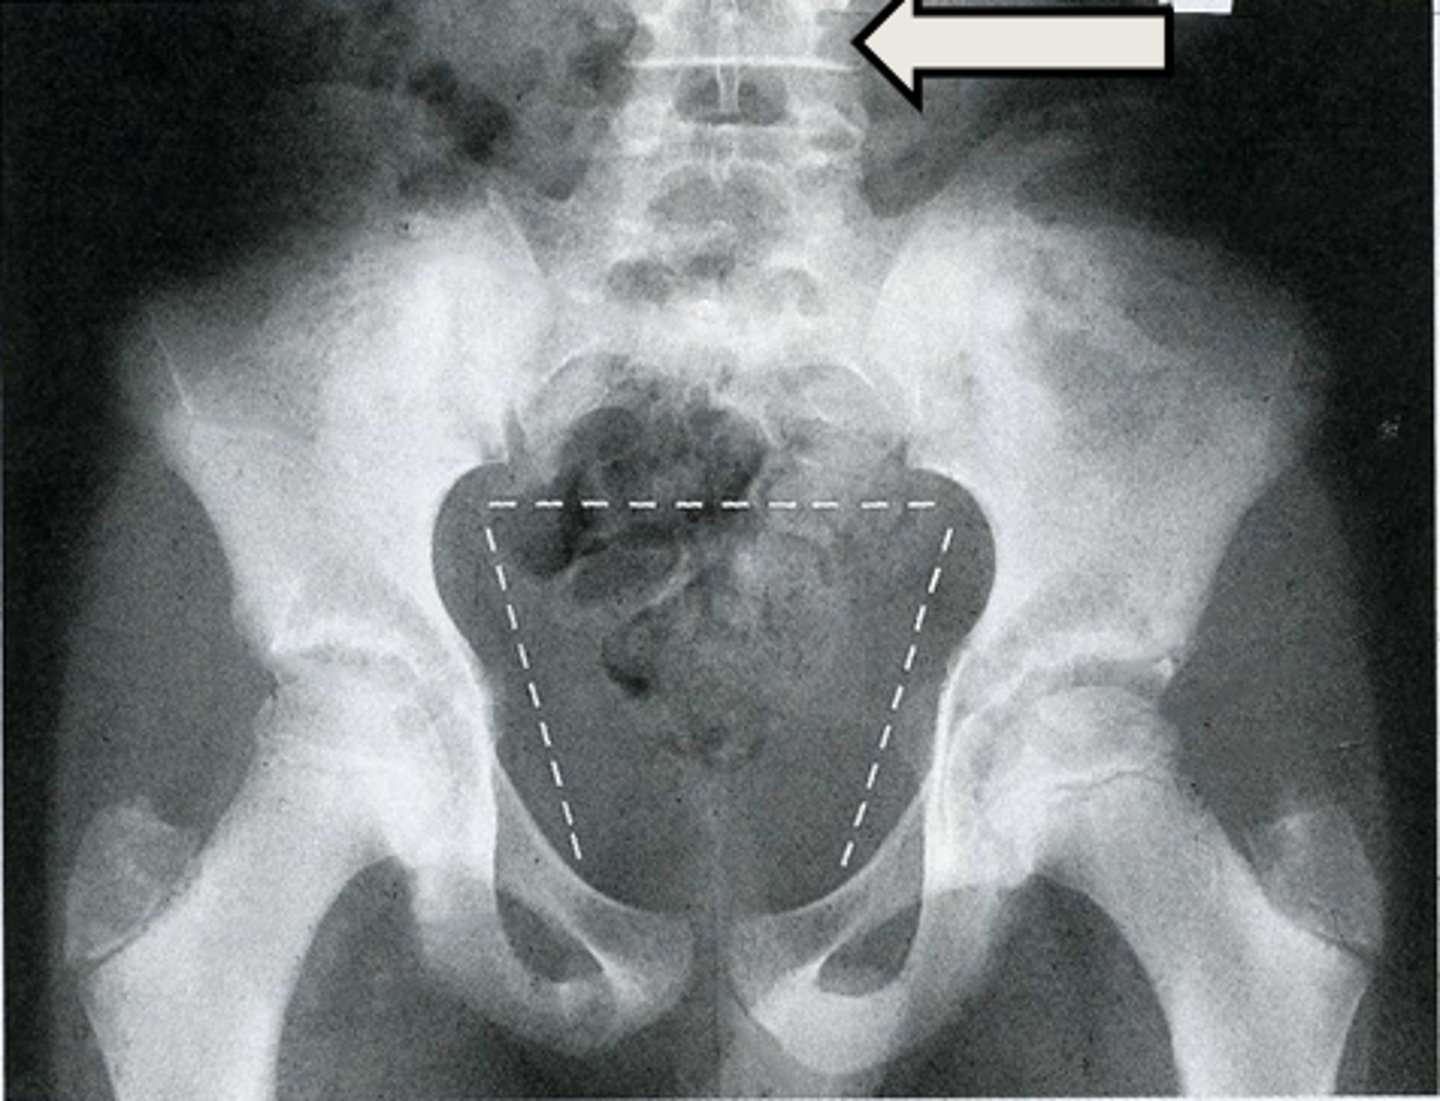

31

New cards

Axial bony pelvis CT

What is the image?

38

L acetabulum

What is indicated in the image?

39

L femoral head

40

L piriformis muscle

41

R femoral head

42

R piriformis muscle

43

R acetabulum (posterior part)

44

Sacrum

<p>What is indicated in the image?</p>